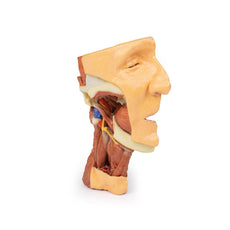

3D Printed Brain Hemisection

This 3D model is a midsagittal hemisection through a whole brain, preserving the right side anatomy and deep brain

structures and spaces visible in the midline. In lateral view, the right cerebral and cerebellar hemispheres are

covered in the arachnoid mater. In the midline view, the brain regions from the cerebrum to the medulla oblongata

are preserved. Centrally, the third ventricle is opened, with an intact septum pellucidum superiorly positioned and

obscuring the lateral ventricles within the cerebral hemisphere. On the inferior margin of the third ventricle both

the right mamillary body and right optic tract can be observed, whereas posteriorly the cerebral aqueduct can be

observed extending across the midbrain between the tectum and tegmentum towards the fourth ventricle (between the

cerebellum and pons). The cerebellum is separated from the occipital lobe by a preserved portion of the tentorium

cerebelli, and in cross-section the cerebellar cortex helps form the prominent arbor vitae.

A series of arterial

branches have been false coloured to contrast their course across the preserved brain structures. In the midsagittal

view the anterior cerebral artery courses from around the corpus callosum to supply the cingulate gyrus and other

midline cortical regions. The base of the middle cerebral artery can be seen passing deep between the temporal and

frontal lobes, with the posterior communicating artery connecting it to a small remnant of the posterior cerebral

artery. Adjacent to the posterior cerebral is the superior cerebellar artery, extending laterally to pass between

the temporal lobe and the cerebellum before passing deep into the transverse fissure.